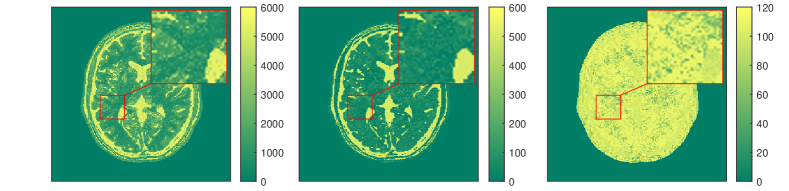

The results for each of the above mentioned algorithms can be found in Figures 3 and 4. We use the MRF reconstruction as initialization for the L-M algorithm, and compare that with the result of the BLIP algorithm when using a relatively refined dictionary. The advantage of integrated-physics approaches is evident by checking the reconstructions in Figure 3 as well as quantitatively by looking at the error maps in Figure 4. In this example, we have used a time series of the 1/8 Cartesian-subsampled k-space data (Fourier coefficients of magnetizations) of length 40. In the original MRF algorithm (typically requiring a large time series of k-space data), this test setting is far from yielding a reasonable result, while BLIP has improved a little by enforcing the projection to the Bloch manifold. But still one observes deficiencies. The method with integrated physics, however, appears to be efficient and it returns the best results among the three methods.

The results in [57] show that the proposed integrated physics model can work well for settings where an explicit solution formula for the Bloch equations is available. However, in most cases (excitation sequences) the Bloch equations have no explicit solution formula. In addition, from a practitioners perspective the Bloch equations appear to be only a simplified mathematical model under some assumptions. As in reality these assumptions are often not realistic, one indeed requires a more complex model. In this vein, deep learning turns out to be a useful data-driven technique for learning or approximating such physical models. In Subsection 3.3 we will therefore discuss extracting physical laws from data.